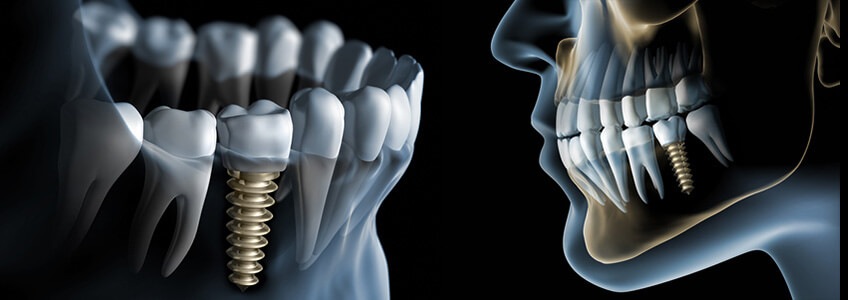

Tedavi Planlaması. Konjenital olarak olmayan, travma veya dental hastalıkla kaybedilmiş, eksik dişlere sahip hastalar için, tek diş implantlar, tercih edilen restorasyon metodudur. Özellikle kayıp ön dişlerin yerleştirilmesinde, komşu dişler çürükse ve full köprü yapmakta kararsız kalındıysa, bu tedavi etkileyici bir seçimdir. İmplantın yer miktarı için 3 önemli durum tanımlanır: implantın kendisi için gerekli yer, estetik ve oklüzyon.

İmplantın başarılı yerleştirilmesi için, implant ile komşu diş arasında, hem diş hem de interproksimal kemik için yeterli yer olmalıdır. En dar implant, shoulder veya platformda 4 mm genişliğindedir. Düzenli iyileşmeye izin vermek ve papillaya uygun yer sağlamak için implant ile komşu diş arasında yaklaşık olarak 1 mm olmalıdır, bu yüzden en az boşluk 6 mm.dir. Boşluk sadece sırtın kretinde değil, komşu dişlerin kökleri arasında da olmalıdır. İmplantın cerrahiyle köke ve apikal dokulara zarar vermeden cerrahisine izin vermesi için, komşu dişlerin apeksleri yeterince uzak olmalıdır.